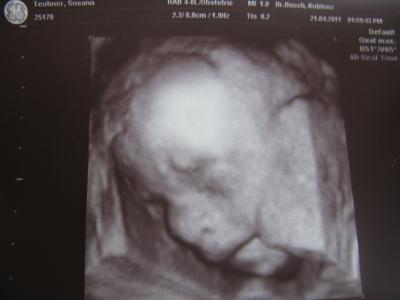

Hey ihr lieben, wir waren heut bei der FD und zum Glück ist alles in Ordnung. Das einzige was war, ist das der Kopf und der Bauch unseres kleinen etwas größer ist als normal. Aber das ist nicht weiter schlimm. Haben halt kein norm Baby. Achja und ganz schön schwer ist er auch, er wiegt 685g (das hat er vom Papa geerbt). So und nun genießen wir noch ein bisschen die Sonne zum Bräunen damit wir zur Hochzeit nicht wie ne Kalkwand aussehen. Liebe Grüße Susi + Sohnemann

Bild zu Zurück von der FD - Forum für August - Mamis